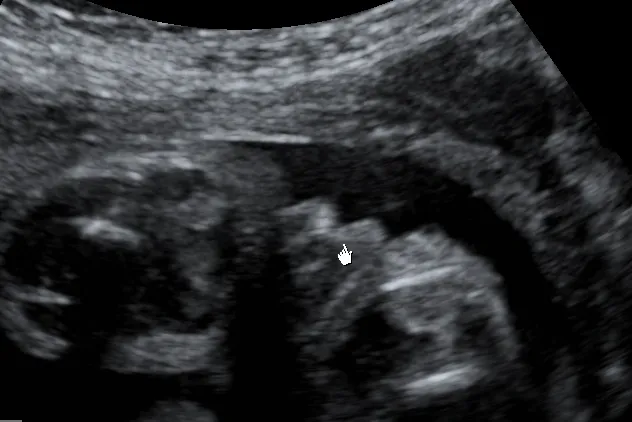

Badanie ultrasonograficzne, czyli popularne USG, jest bez wątpienia podstawową i najczęściej stosowaną metodą określania płci dziecka. Dlaczego? Ponieważ jest to metoda nieinwazyjna, bezpieczna dla matki i dziecka, a przy tym bardzo skuteczna. Pozwala nam, lekarzom, na bezpośrednią wizualizację rozwijającego się płodu i jego narządów, w tym także narządów płciowych.

Pierwsze badanie USG, które może dać nam wgląd w płeć dziecka, to tak zwane USG genetyczne, wykonywane między 11. a 14. tygodniem ciąży. Chociaż narządy płciowe są już wtedy wstępnie uformowane, a doświadczony ultrasonografista może czasem dostrzec pewne wskazówki, to jest to nadal bardzo wczesny etap. Ryzyko pomyłki jest wtedy znacznie większe niż w późniejszych tygodniach. Z mojego doświadczenia wynika, że najwcześniejszy wiarygodny termin, przy sprzyjających warunkach, to około 14. tydzień ciąży.

Absolutnie najlepszym i najbardziej wiarygodnym czasem na poznanie płci dziecka jest badanie USG połówkowe, przeprowadzane zazwyczaj między 18. a 22. tygodniem ciąży. W tym okresie maluszek jest już na tyle duży, że jego narządy płciowe są dobrze rozwinięte i łatwiejsze do zidentyfikowania. Przy dobrym ułożeniu dziecka i odpowiedniej jakości sprzęcie, skuteczność określenia płci wynosi ponad 95-99%. To właśnie wtedy najczęściej możemy z dużą pewnością powiedzieć, czy spodziewacie się chłopca, czy dziewczynki.

Nie mogę też nie wspomnieć o znaczeniu jakości sprzętu USG oraz doświadczenia i umiejętności lekarza wykonującego badanie. Nowoczesne aparaty ultrasonograficzne oferują znacznie lepszą rozdzielczość obrazu, co ułatwia dostrzeżenie drobnych szczegółów. Jednak nawet najlepszy sprzęt nie zastąpi wprawnego oka i wiedzy specjalisty, który potrafi odpowiednio zinterpretować widziany obraz i odróżnić, na przykład, pępowinę od prącia.